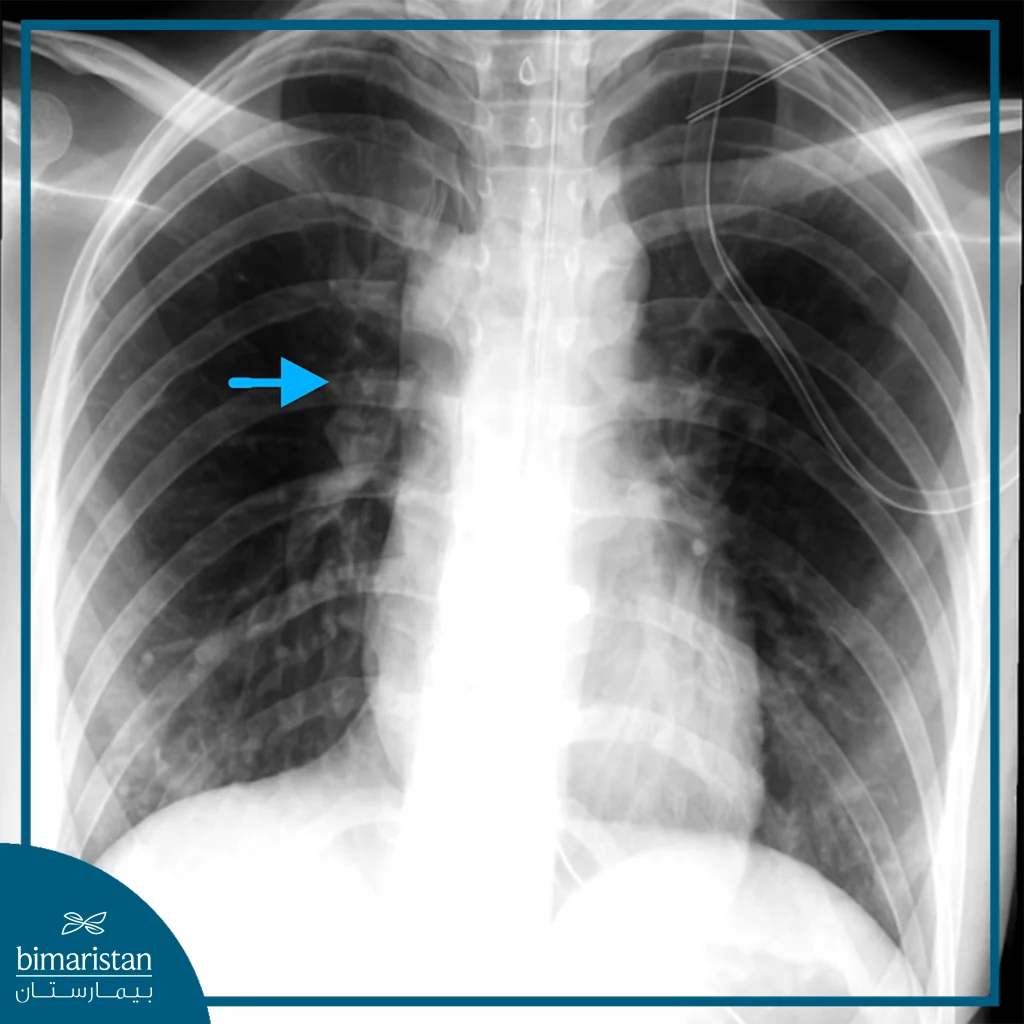

Chest X-ray

It is the first imaging step and may show air in the mediastinum, pleural effusion, mediastinal shadow dilatation, subcutaneous air, or free air under the diaphragm in cases of abdominal perforation.